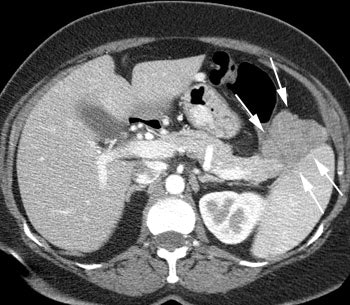

VIPoma: The patient shown below presented for evaluation of a 9 month history of intractable diarrhea and an elevated VIP level. Previous conventional imaging studies had been negative. The In-111 Octreotide study demonstrated a large area of intense uptake within the pancreatic tail (black arrow on transaxial SPECT images). Repeat CT imaging confirmed the presence of a VIPoma within the pancreatic tail (white arrows). |

|